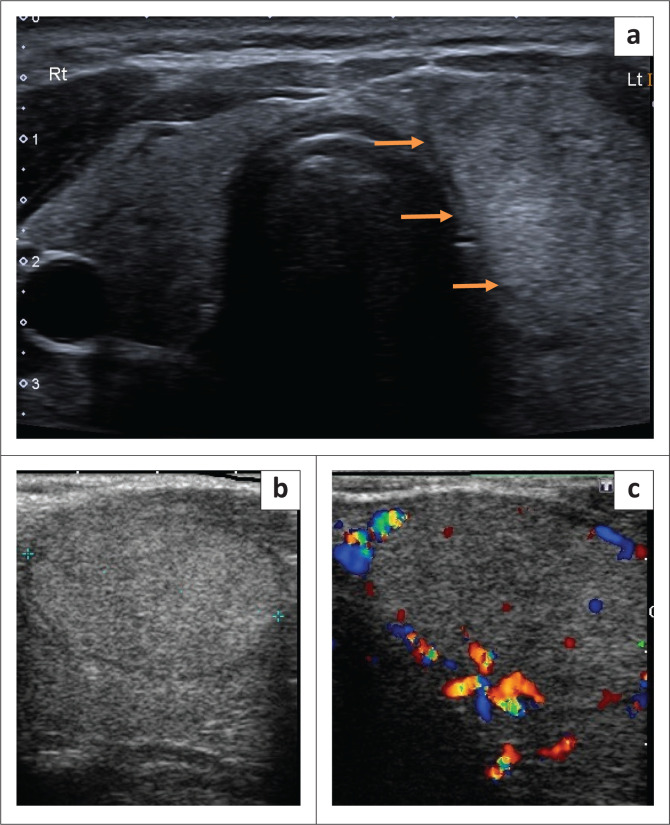

Thyroid gland vascular proliferations pose a challenge to pathologists, radiologists and surgeons. This is illustrated in the case of a 36-year-old woman who underwent a diagnostic thyroid lobectomy for a suspected follicular neoplasm according to cytology. Histological diagnosis confirmed a follicular adenoma as well as a cavernous haemangioma or venous malformation.

Contribution: Thyroid vascular lesions are rare. Evolving nomenclature and application of the International Society for the Study of Vascular Anomalies classification are discussed. Pertinent radiological clues are highlighted to pre-empt the diagnosis and avoid potential surgical complications.